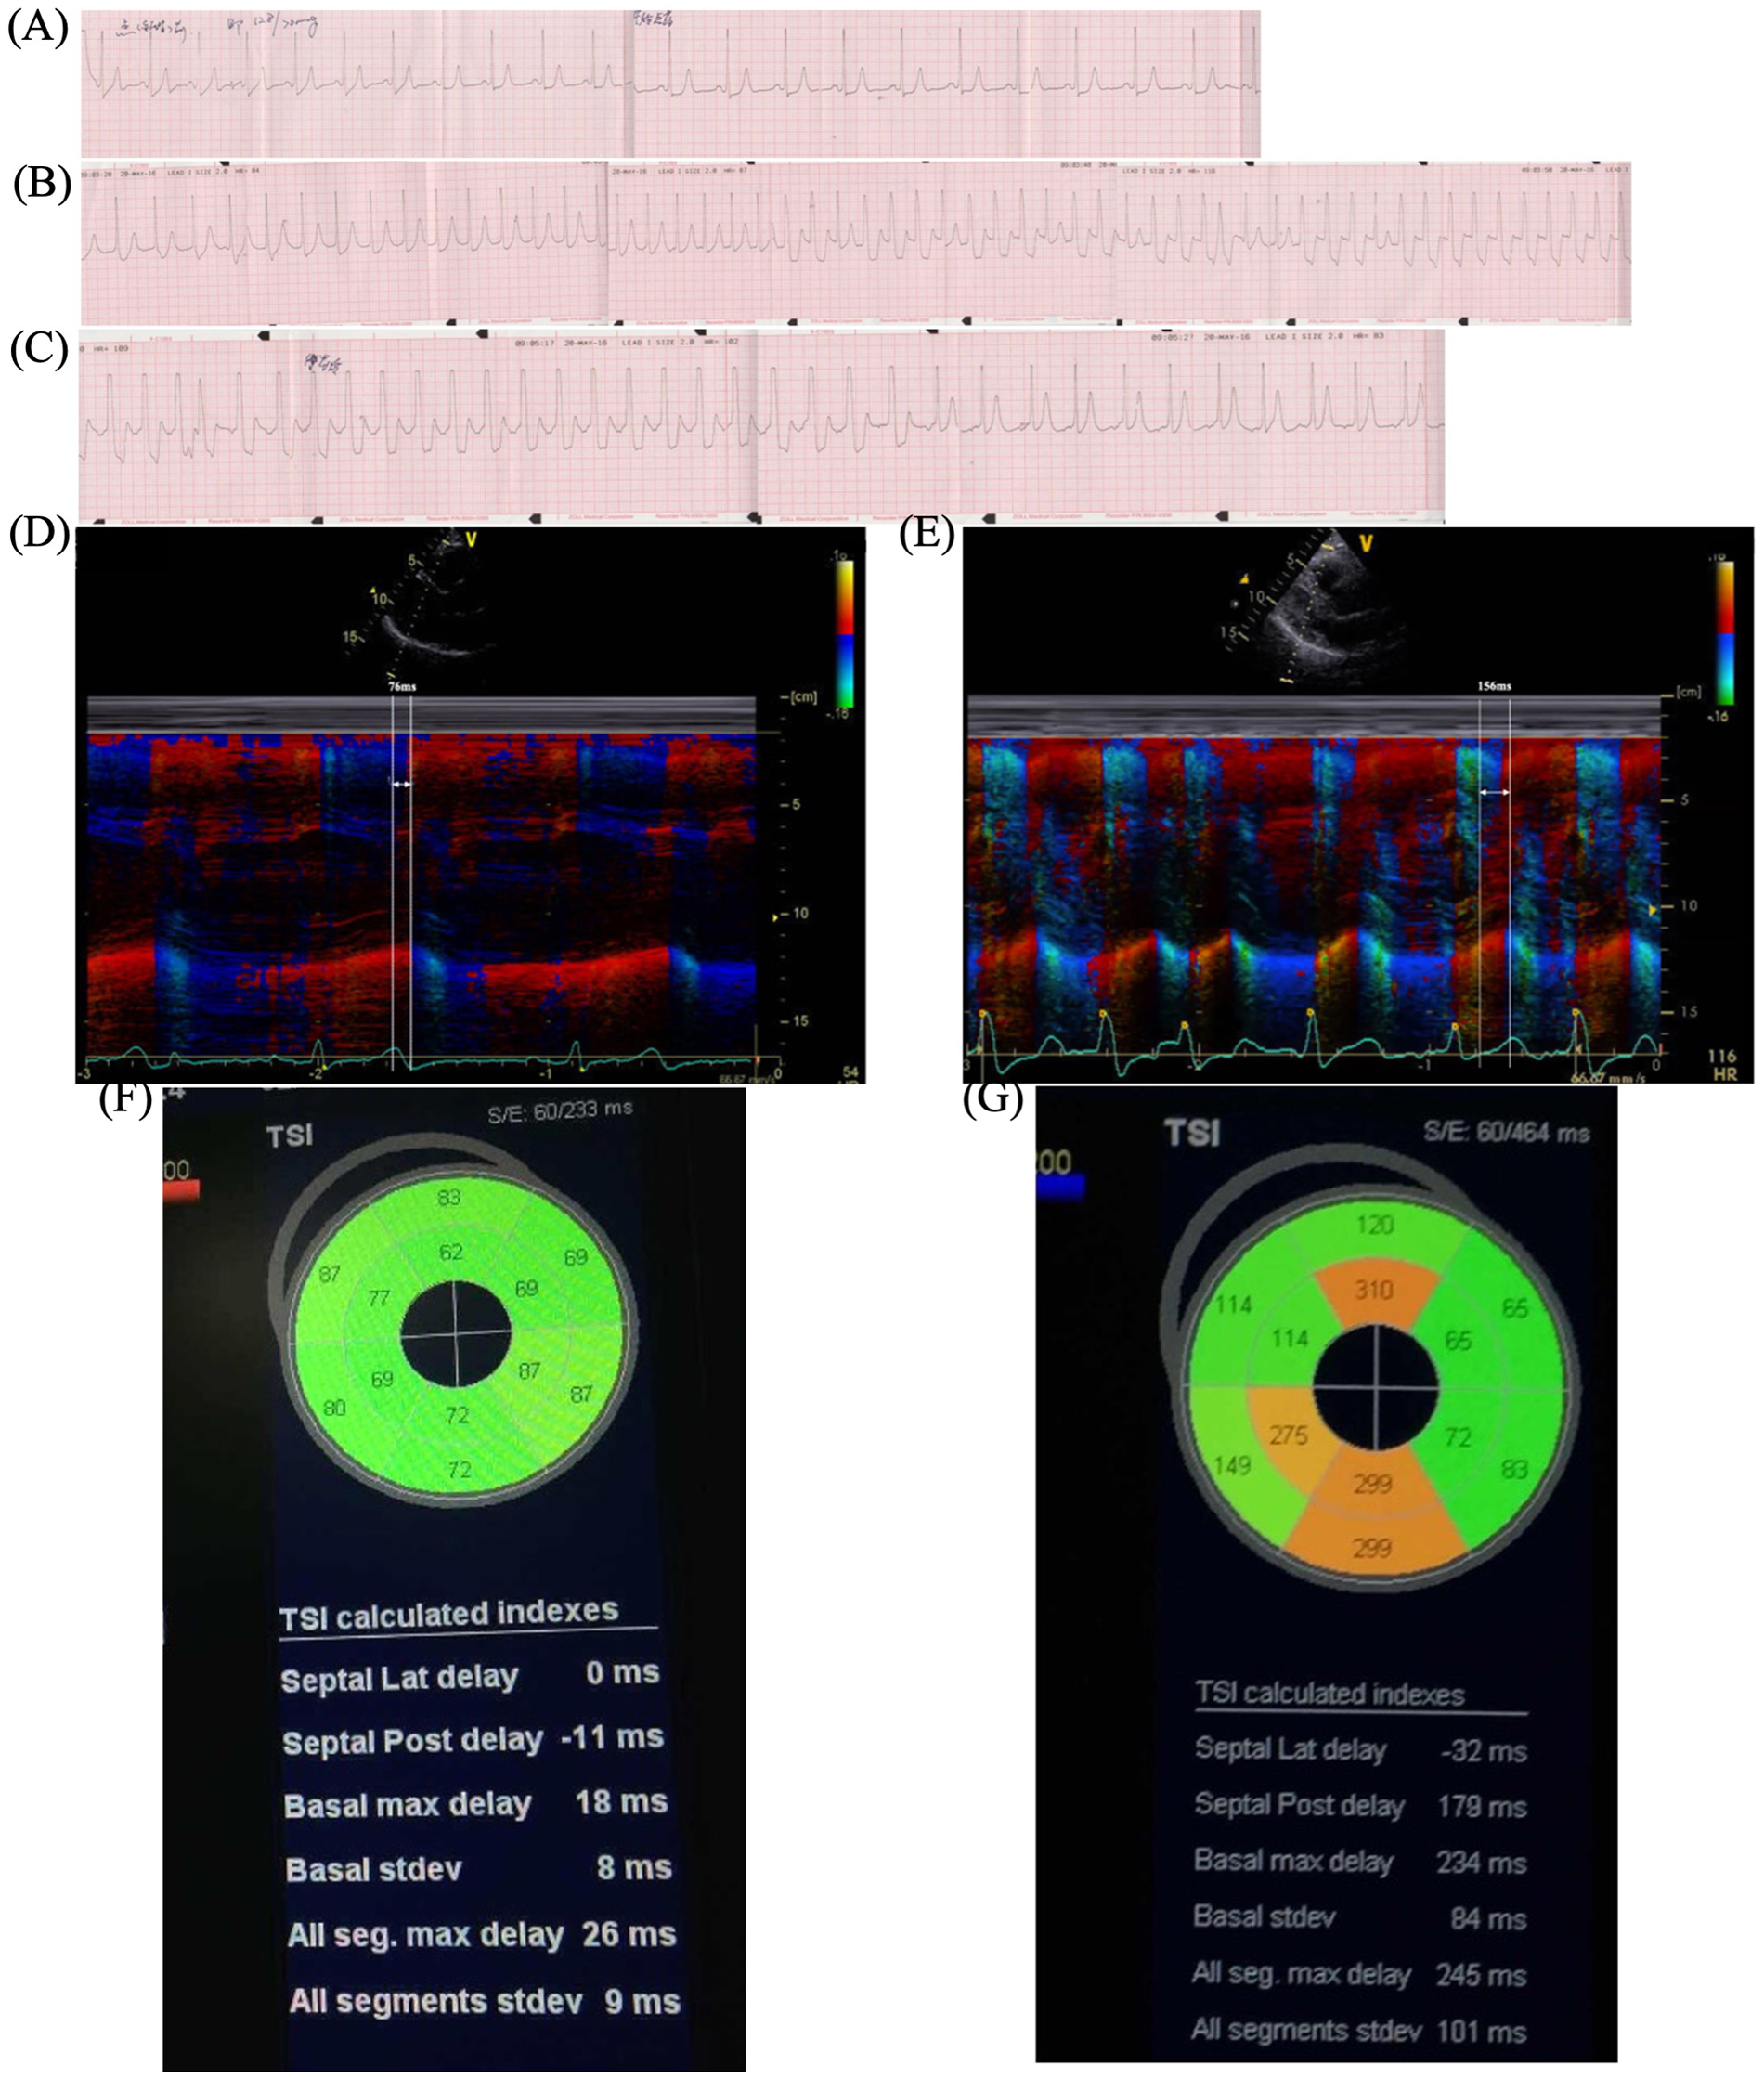

To simulate the scenario, isoprenaline (ISO) stress UCG was performed. The continuous ECG monitoring showed the new-onset LBBB when her HR increased from 60 to 120 bpm, and chest pain recurred simultaneously (Figures 2A,B). Furthermore, the stress UCG suggested an increase in septal-to-posterior wall motion delay (SPWMD), anteroseptal-to-posterior wall delay (ΔTS), and aortic pre-ejection interval–pulmonary pre-ejection interval (APEI-PPEI), which indicated interventricular and intraventricular desynchrony (Figures 2D–G, Table 1). The patient’s chest pain and LBBB disappeared when her HR decreased to 80 bpm after terminating ISO (Figure 2C).

Figure 2

ISO stress UCG test. (A) Baseline ECG before ISO. (B) New-onset LBBB after ISO when HR increased to 120 bpm and chest pain recurred. (C) LBBB and chest pain disappeared when HR decreased to 80 bpm after stopping ISO. (D) Color tissue Doppler M-mode UCG showed baseline SPWMD was 76 ms. (G) Post-ISO SPWMD increased to 156 ms. (F) Baseline TSI. (G) Post-ISO TSI. ISO, isoproterenol; UCG, echocardiography; ECG, electrocardiography; LBBB, left bundle branch block syndrome; BPM, beats per minute; HR, heart rate; SPWMD, septal-to-posterior wall motion delay; TSI, tissue synchronization imaging.

Stress UCG can increase HR and evaluate the hemodynamic changes during rate-dependent LBBB. SPWMD of M-mode echocardiography and ΔTS of tissue synchronization imaging (TSI) are useful approaches to quantify intraventricular desynchrony, with the cut-off values of greater than or equal to 130 and 65 ms, separately (8, 9). Interventricular desynchrony can be measured as APEI-PPEI, measured as the time from the onset of the QRS to the onset of pulsed Doppler flow velocities in the LV and right ventricle (RV) outflow tracts respectively, with cut-off values of greater than or equal to 40 ms (9). Consistent with the above, our patient's post-ISO UCG showed significant increases in parameters (SPWMD 76 vs. 156 ms, ΔTS 26 vs. 245 ms, APEI-PPEI 3 vs. 52 ms), which meant interventricular and intraventricular desynchrony during LBBB.